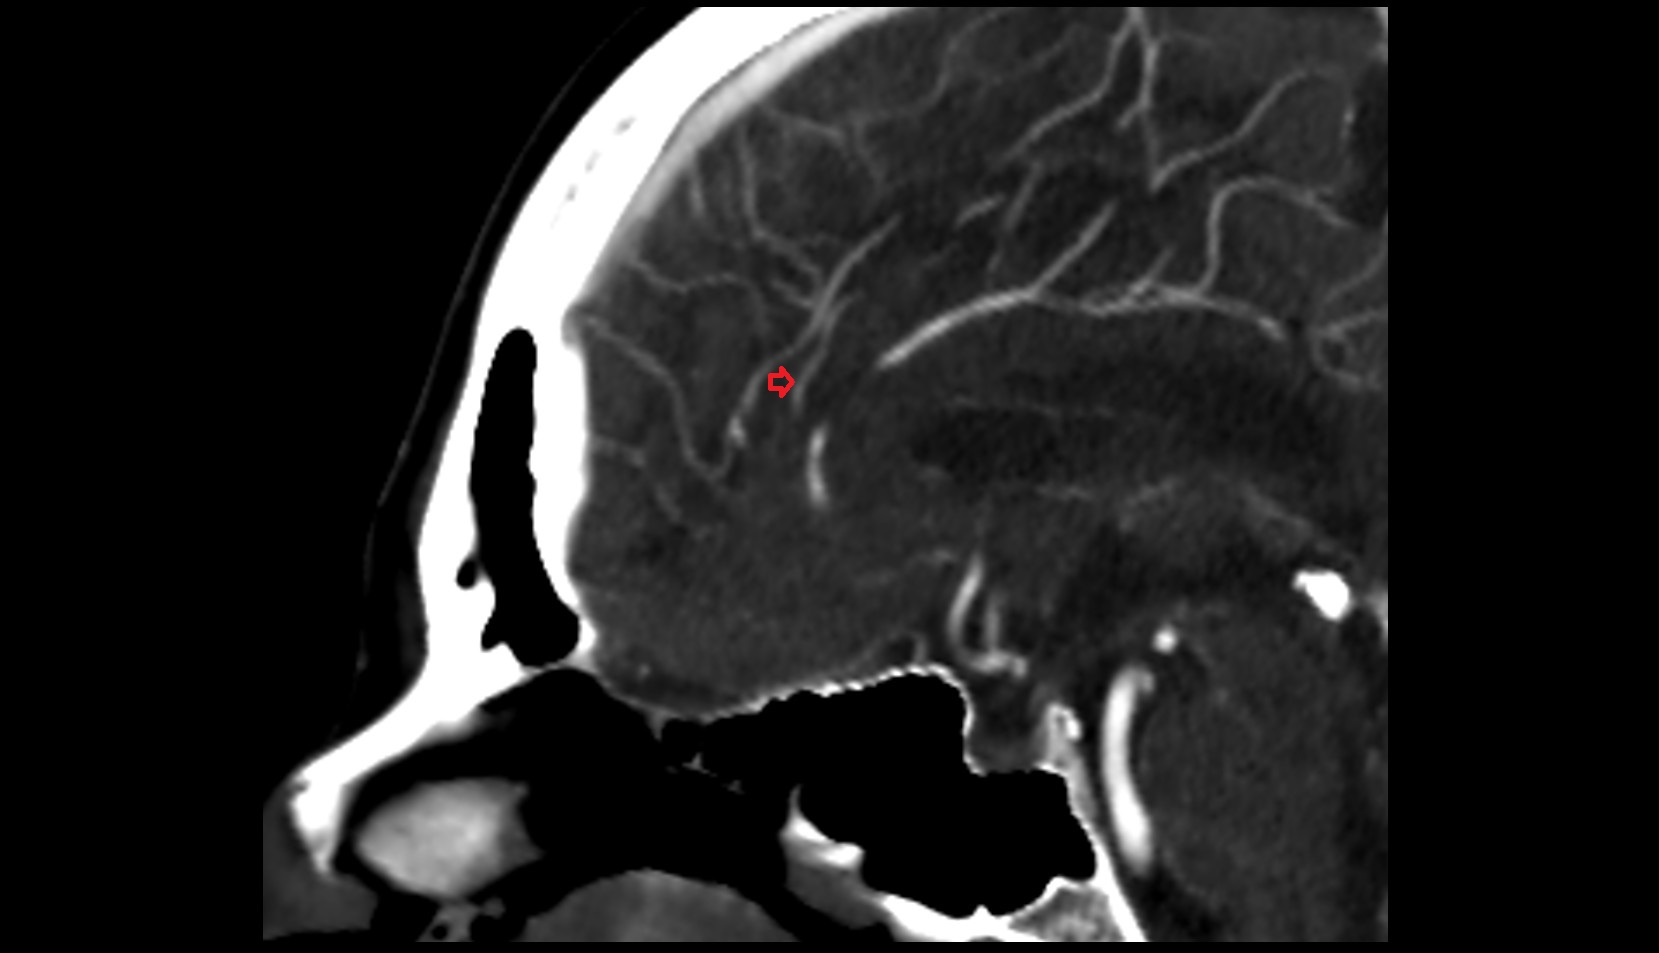

- Middle cerebral artery

- Middle cerebral artery horizontal segment (M1)

- Middle cerebral artery insular segment (M2)

- Middle cerebral artery opercular segment (M3)

- Middle cerebral artery cortical segment (M4)